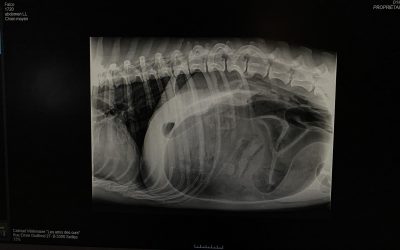

Le syndrome de dilatation torsion d’estomac est une urgence vitale à voir au plus vite. La vie de l’animal est en jeu à chaque minute.

Les chiens comme les chats sont très curieux. C’est un de leurs vilains défauts car ils ont tendance à ingérer n’importe quoi! Chaussette, culotte, guirlande, os, tout peut y passer. Cela devient alors un corps étranger. Parfois cela reste coincé au niveau de la gueule ou de la bouche mais parfois cela continue son chemin dans le tube digestif. Ca a été le cas pour Koeurly. Il faut alors intervenir rapidement!